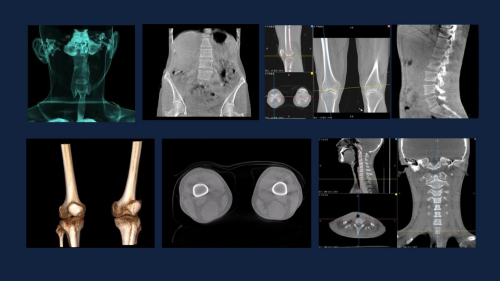

此外在日益增长的脊柱侧弯患者前,WR-3D的全脊柱三维扫描重建功能能提供更加丰富的临床信息,众所周知目前临床在评价脊柱侧凸的主要方法有Cobb角测量法、终板法和椎弓根法,在Cobb角测量之外,脊柱旋转定量测量也是临床非常重要的评估信息,而在立位三维状态下的脊柱评估能更为真实的反应脊柱侧凸的问题。WR-3D通过三维全脊柱扫描,无需进行角度拼接,即可完成脊柱三维影像重建,消除二维Cobb角度测量的误差,可以实现包括Cobb角、前/后凸角、椎体偏移/旋转向量图、椎体旋转角条形图、矢/冠状面垂直轴偏距数据的自动测量;这项技术将为脊柱矫形的临床诊断带来从定性到定量的转变,提供丰富的数据和图表,为临床尤其是手术方案的规划制定提供非常精准的定量化数据支撑,不仅可以对脊柱冠状面参数进行精准的定量评估,还可对矢状面包括,颈椎前凸、后凸、腰椎前凸和后凸进行非常精准的评估。

以上可以看到WR-3D给临床检查提供了更丰富的信息,据了解WR-3D技术还可以完成多部位的三维扫描重建,例如像颈椎曲度改变的立位三维状态评估、全下肢三维容积扫描重、寰枢椎半滑脱、拇外翻的测量与诊断等等。